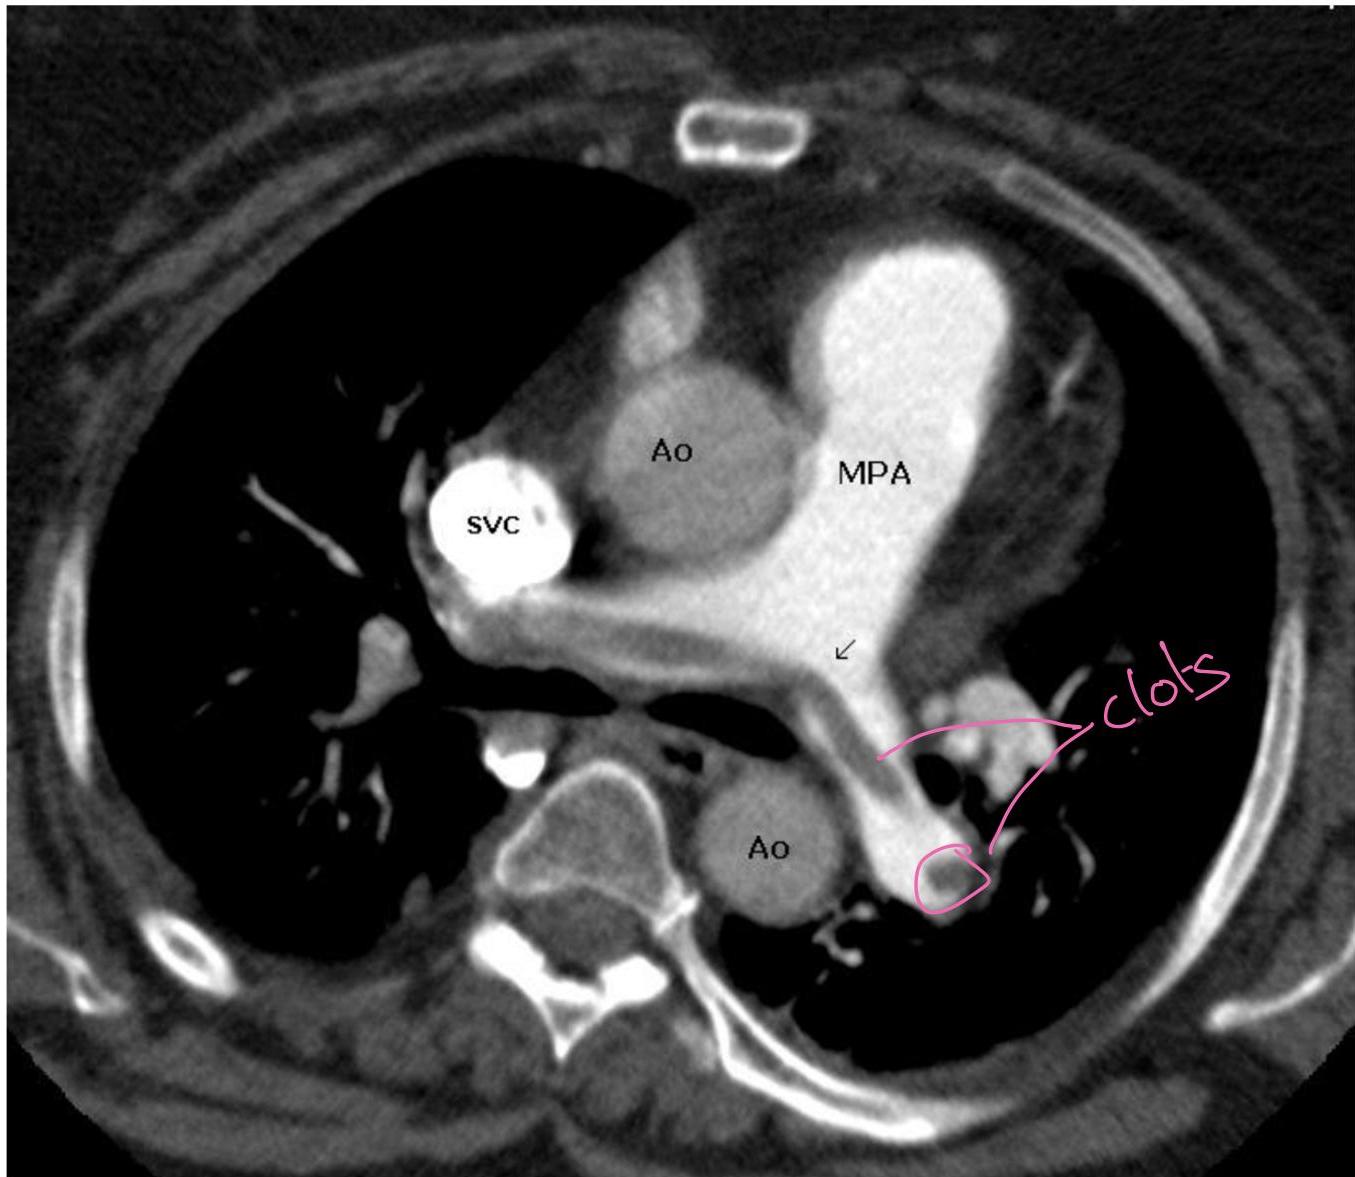

Case 1: Pulmonary Embolism (PE)

- Presentation: 62F, 3 weeks post-right THA, admitted for COPD exacerbation. Sudden onset L-sided chest pain (8/10), pleuritic, O2 sat drop (94% â 88% on 2L NC).

- Labs: Positive D-dimer, Troponin 0.12 (Normal < 0.04), BNP 520.

- Management Plan: Give heparin (âheforinâ [sic]) and send to CT.

- Treatment: Anticoagulation (Heparin/LMWH). Thrombolytics in hypotensive/massive PE. IVC filter if bleeding risk.

Diagnostic testing

- Pulmonary angiography (Gold standard)

- Spiral CT (CT-PE protocol)